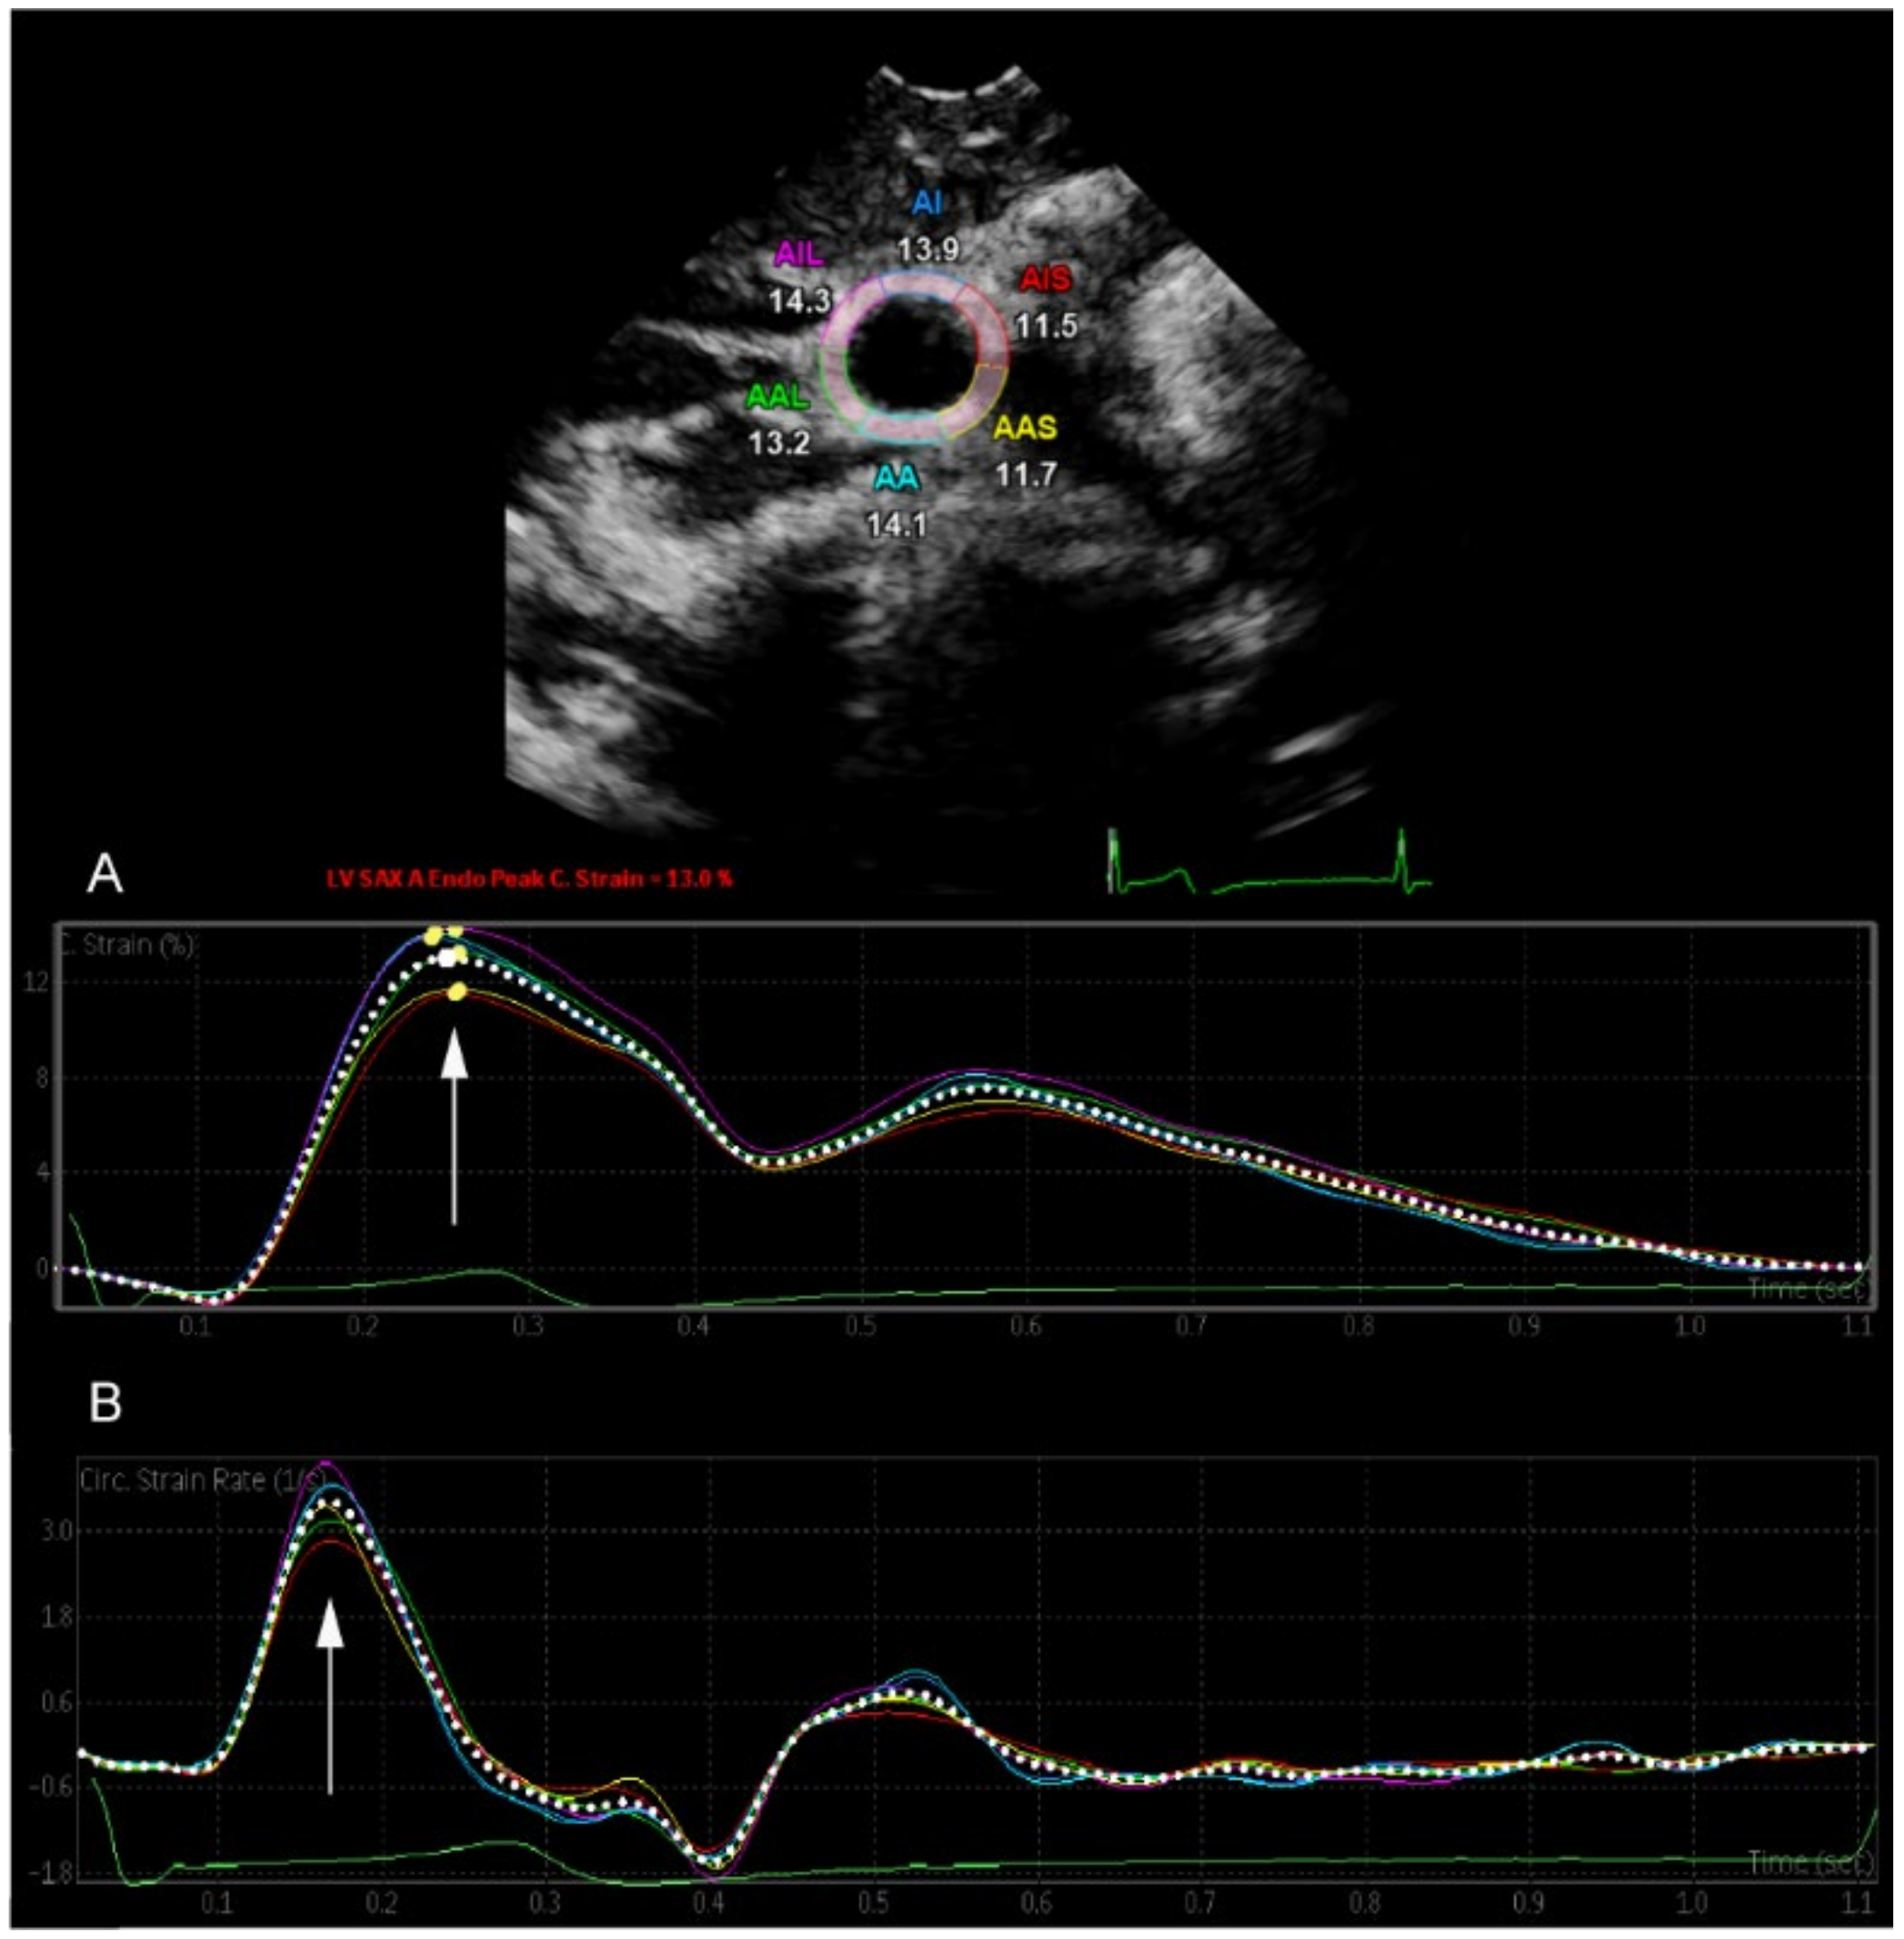

2.4. Two-Dimensional Speckle Tracking of the Common Carotid Artery

3.2. Acute Effects of Energy Drinks on CS, SR, and Arterial Distensibility

| CCA CS (%) | 12.37 ± 3.01 | 12.29 ± 2.76 | 0.89 |

| CCA SR (s−1) | 3.23 ± 0.73 | 3.24 ± 0.73 | 0.94 |

| Arterial Distensibility (mmHg−1 × 10−3) | 538.68 ± 135.25 | 519.94 ± 117.22 | 0.49 |

| CCA CS (%) | 11.78 ± 2.70 | 12.29 ± 2.68 | 0.043 * |

| CCA SR (s−1) | 3.20 ± 0.73 | 3.34 ± 0.74 | 0.087 |

| Arterial Distensibility (mmHg−1 × 10−3) | 504.69 ± 145.50 | 521.92 ± 134.99 | 0.313 |